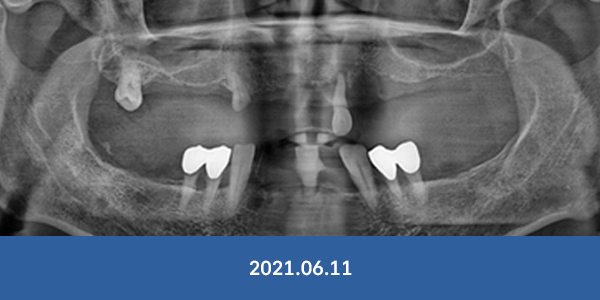

풍부한 임상 경험을 가진 대표원장이 처음 상담부터

수술, 사후관리까지 전 과정 직접 책임집니다.

정확한 진단과 안전한 수술로 오래 쓰는 임플란트를 약속드립니다.

전체 임플란트 중

실제 뼈이식이 필요한 경우단 20%

POINT 01

이정웅 원장의

실제 뼈이식률은 단 10%

광고와 실제 비용이 다른 병원과 달리,

서울감동치과의 임플란트는

숨겨진 추가 비용 없이 69만원에 시술받으실 수 있습니다.

풍부한 임상 경험과 노하우로 뼈이식률을 낮추고,

환자 부담을 줄이면서도 안정적인 결과를 약속드립니다.